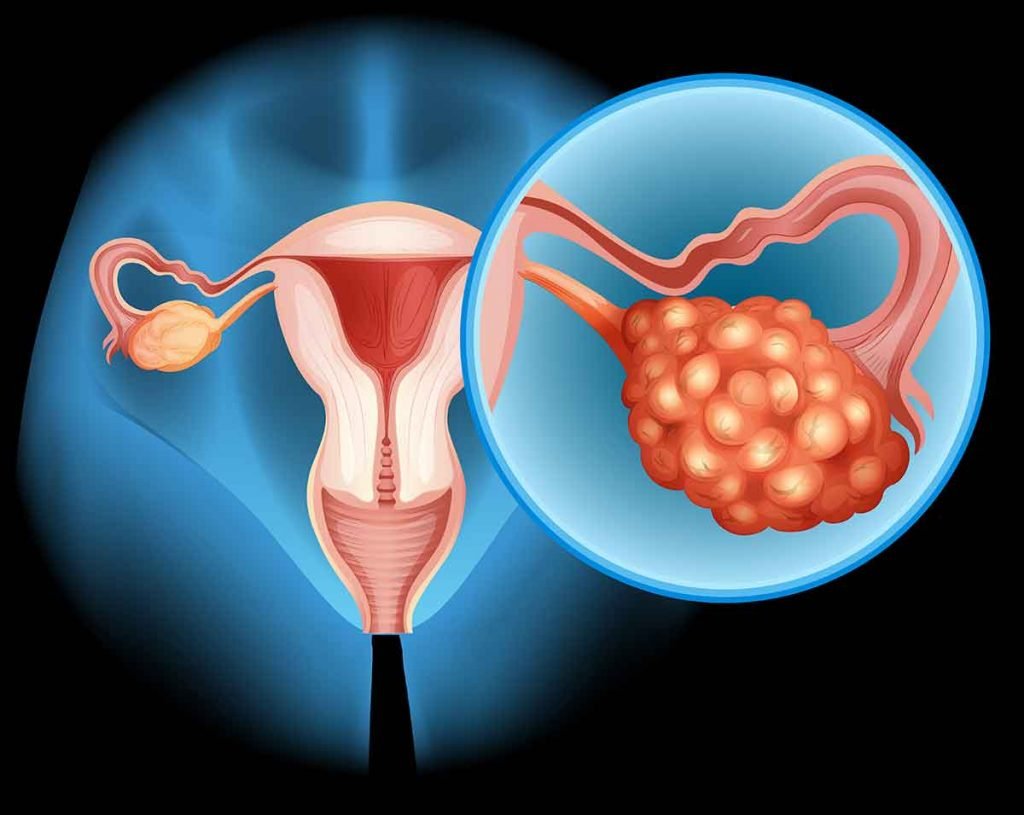

Síndrome de Ovario Poliquístico (SOP): Mucho más que periodos irregulares

¿Sientes que tu ciclo menstrual es un caos? ¿Luchas contra el acné adulto o el vello indeseado y